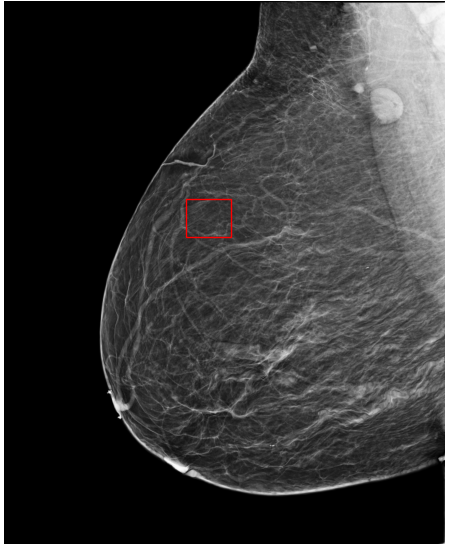

Refer to caption

(a) FeatAlign

(b) FeatAlignReg

(c) ImgFeatAlign/ImgAlign

(d) FeatAlign

(e) FeatAlignReg